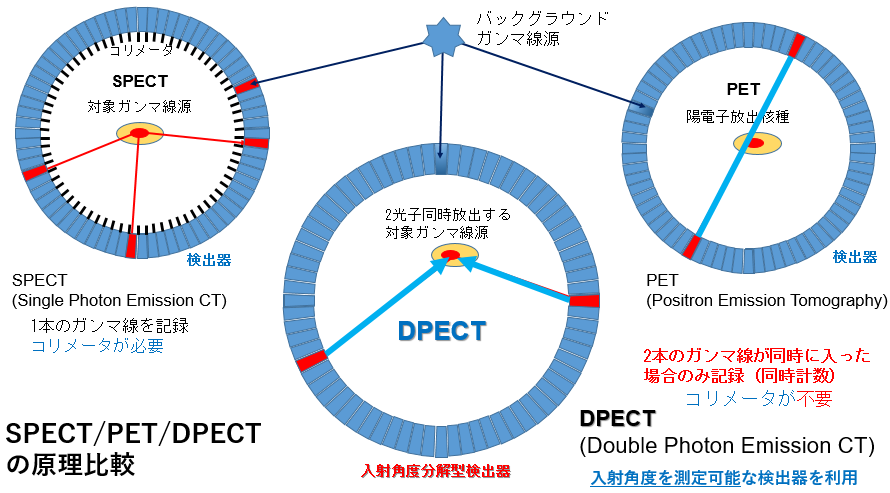

spectの画像